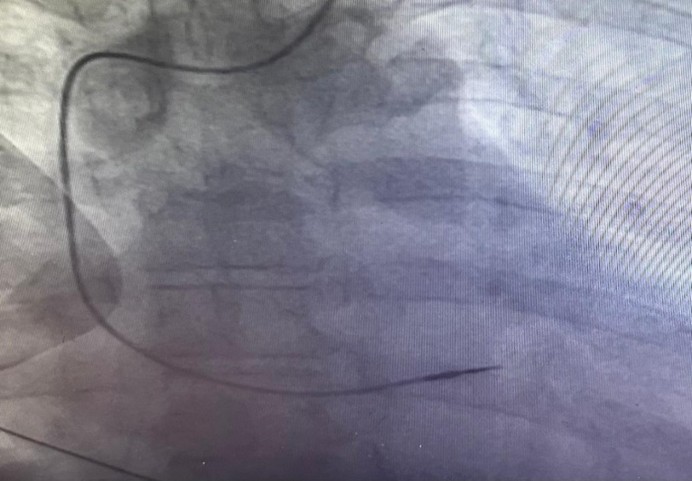

ECG at emergency department revealed loss of capture of pacemaker spikes [Figure 1]. Pacemaker interrogation showed complete loss of pacing and sensing of the ventricular lead. The patient admitted to any manipulation of the pace maker. Fluoroscopy revealed coiling of the pacing lead around the pulse generator [Figure 2]. The pacemaker pocket was reopened. Fortunately, both the insulation and the conductor of the lead were intact. The same lead was repositioned and proved to be functional with good pacing and sensing parameters [Figure 3]. The pulse generator was fixed on the pectoral muscle with non-absorbable sutures. No further complications were detected in one year follow-up.

Details from a fluoroscopy showing the coiling of the pacing lead around the pulse generator of a pacemaker.

2C&2D: The same lead was repositioned and proved to be functional with good pacing and sensing .